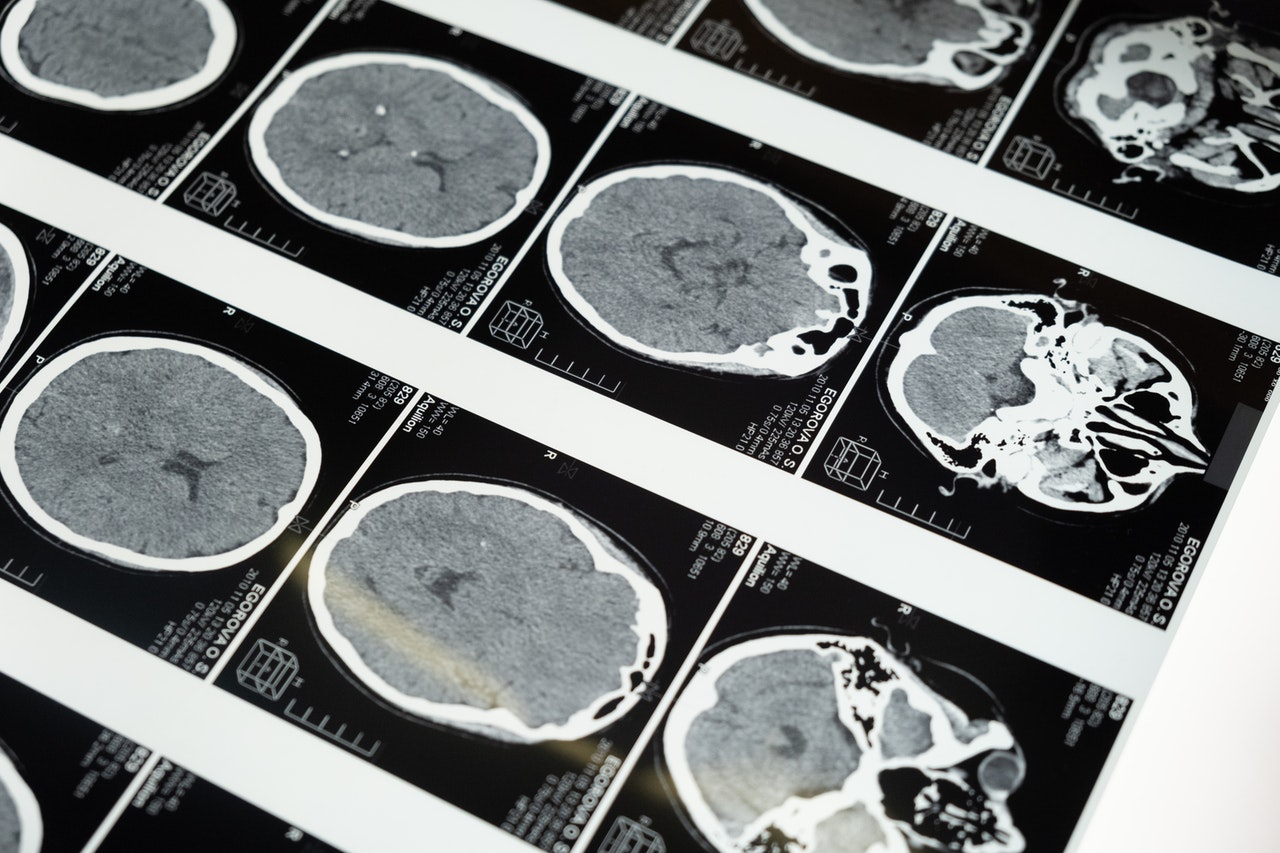

La funzione originaria dei sistemi di risonanza magnetica era associata allo studio del sistema nervoso centrale. Con il tempo, alla luce dei risultati ottenuti, sono stati utilizzati anche per altri distretti del corpo, come muscoli, articolazioni, addome, torace e scheletro.

I pazienti riescono a trarre vantaggio da questa forma di diagnosi poiché rileva, in modo preciso e non invasivo numerose malattie o lesioni interne al corpo. La risonanza magnetica, infatti, viene oggi impiegata per lo studio di malattie infettive, tumorali, infiammatorie, patologie traumatiche o degenerative. Questo strumento è in grado di rilevare un ampio spettro di disturbi, malformazioni o patologie che possono compromettere il regolare funzionamento dell’organismo umano.

Per ottenere immagini di un particolare distretto corporeo, il sistema di risonanza magnetica si serve di un magnete ad alto campo (lo standard diagnostico dei sistemi RM è 1.5T attualmente) che generando un campo magnetico agisce sui nuclei degli atomi che costituiscono il corpo umano, allineandoli con la direzione delle linee di campo del magnete stesso.

I nuclei vengono poi eccitatati mediante un sistema a radiofrequenze che turba il loro stato di equilibrio. I nuclei eccitati, tornando poi al loro stato di quiete originario, emettono un segnale recepito da apposite antenne, dette bobine, che viene poi convertito in segnale digitale e, grazie ad appositi computer, si elabora l’immagine diagnostica.